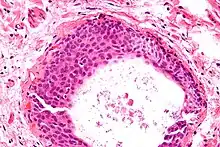

Micrograph of a Walthard cell nest, the entity Brenner tumours are thought to arise from. H&E stain.

Histologically, there are nests of transitional epithelial (urothelial) cells with longitudinal nuclear grooves (coffee bean nuclei) lying in abundant fibrous stroma.